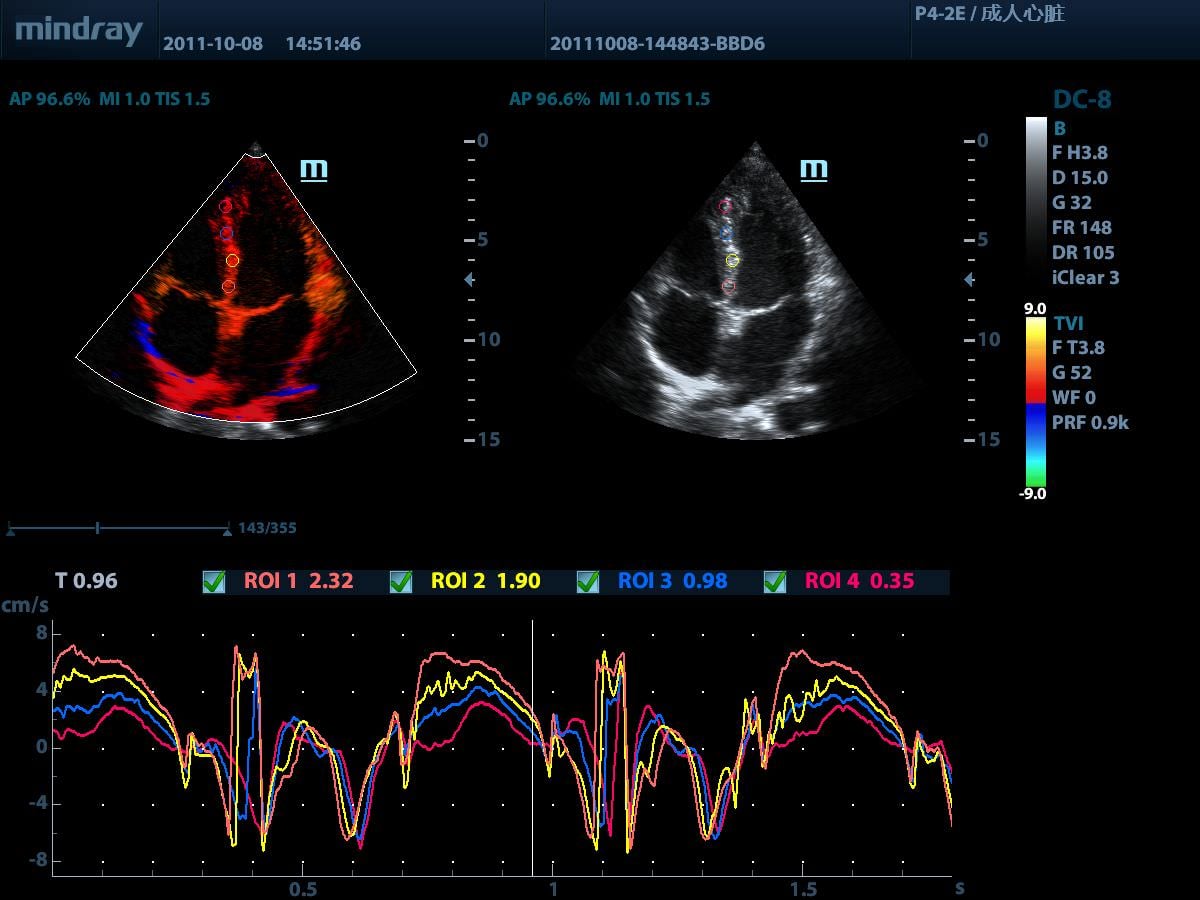

Тканевой допплер (TDI (доплеровская визуализация движения тканей), включая TDI-Color (цветовой TDI), TDI-Power (энергетический TDI), TDI-M (TDI c M-режимом), TDI-PW (импульсно-волновой TDI))

Функция позиционирования тканей с количественным анализом

Простое, быстрое и неинвазивное решение для выявления нарушений локальной сократимости участков миокарда. Позволяет существенно повысить точность и эффективность позиционирования, практически полностью контролируя смещение изображения в результате движения датчика или дыхания пациента.

Режим деформации / скорости деформации

Позволяет получить полную оценку ишемической болезни сердца посредством визуализации показателей деформации / скорости деформации, обеспечивая детальное сопоставление различных участков миокарда.

Позволяет получить полную информацию о движении сердечной мышцы в различных фазах сокращения и одновременно определять степень синхронизации миокарда. Точность результатов обеспечивается высокой частотой кадров.

Визуализация в режиме тканевой допплерографии (TDI)

Исследование в режиме тканевой допплерографии позволяет определять количественные показатели движения и функционирования сердечной мышцы, предоставляет полный спектр режимов тканевого допплера для уменьшения времени и повышения точности ультразвуковой диагностики.